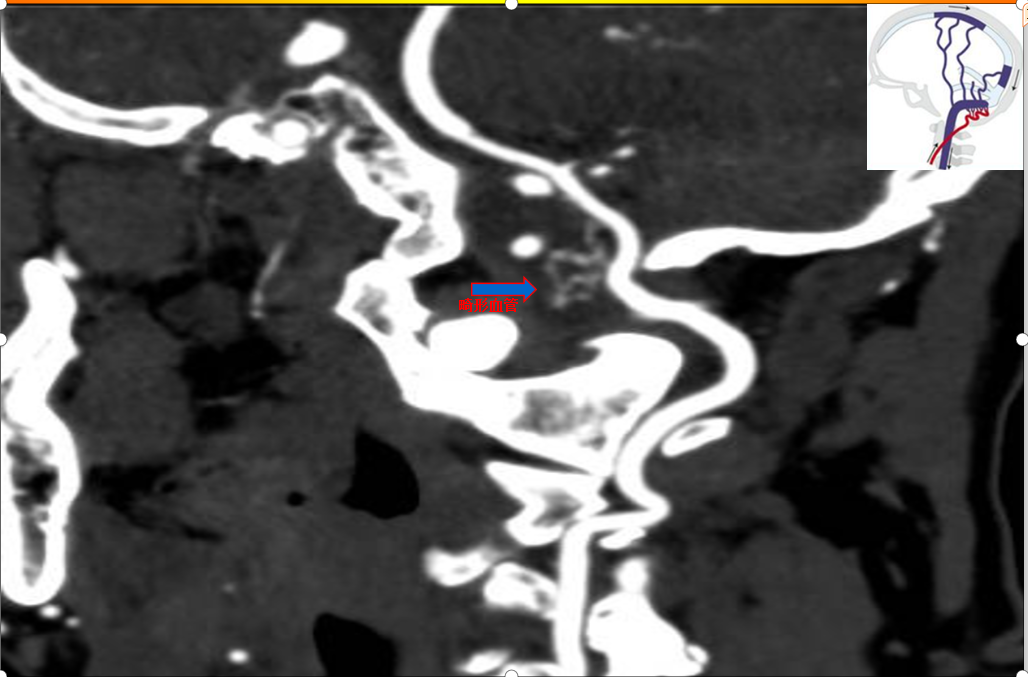

62岁的黄先生因“反复头晕伴呕吐1月余 ”来到柳州市工人医院住院。颅脑MRI及DWI、MRA提示:延髓异常信号灶,考虑动静脉畸形并局部胶质增生,变性可能性大;脑、脊髓血管造影提示:枕颈交界区硬脑膜动静脉瘘,瘘口位于椎动脉硬脊膜入颅处。

术前急诊CT:枕大孔区畸形血管

术前CTA: 颅颈交界区硬脑膜动静脉瘘